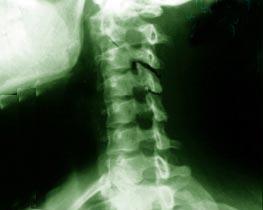

神经根型颈椎病是因单侧或双侧脊神经根受刺激或受压所致,其表现为与脊神经根分布区相一致的感觉、运动及反射障碍,本病较多见,各种有针对性的非手术疗法均有明显的疗效,其中尤以头颈持续(或间断)牵引、颈围制动及纠正不良体位有效。预后大多较好。